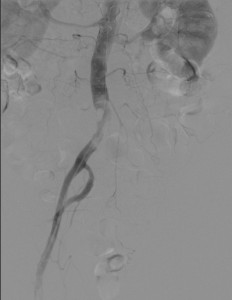

The diagnosis of acute limb ischemia is mainly clinical. A plausible story coupled with signs and symptoms should be enough. Once the diagnosis is suspected ancillary testing can serve to confirm it and to locate the problem. These usually start with a bedside Doppler. The arterial signal should be carefully sought. If it is absent a venous signal should looked for. Absence of a venous hum usually means that the lack of flow is very severe and that edema is present. This is typical of very severe acute limb ischemia. Then an arterial duplex ultrasound is usually used. Finally, angiography is the usual next step. It serves both for diagnosis and for treatment.

Next intervention should be entertained versus observation. In viable limbs, anticoagulation and observation are possible, though treatment is sometimes chosen. In other cases, the level of urgency depends on the degree of limb ischemia. Category IIa can be postponed while category IIb cannot. The specific treatment of acute limb ischemia depends on the cause. For the more common cause of embolism, treatment is either catheter directed lysis or thrombectomy or a combination. If catheter based treatments fail, surgery may be needed. Surgery included endarterectomy, embolectomy and thrombectomy. Surgery should be the first line of treatment for closure device related acute limb ischemia. The reason for this is that often there is a need to remove the device and suture the vessel. As patients with acute limb ischemia are often sick, surgery often results in poor systemic outcomes. Sometimes postponing surgery when possible (category III) will result in better outcome because of comorbidity optimization.